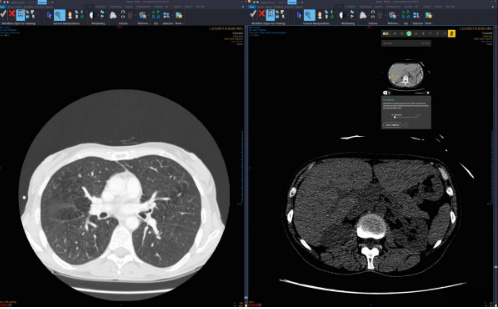

2、医疗成像

20172月,基于云的医学影像管理公司Ambra Health宣布推出面向医学影像的云开发平台Ambra for Developers。这是全球第一个专为医学成像设计的云开发平台。

通过新的API,医疗系统和医院的IT部门可以轻松地将图像扩展到其他应用程序中,如人口健康、报表工具等。此外,第三方开发商可以迅速将Ambra成像技术整合为医疗应用的一部分,为用户提供更好的患者护理。

许多具有前瞻性思维的公司正在利用Ambra的云开发平台来改进其解决方案。包括深度学习、诊断决策、远程放疗、专业图像分析等方面。Ambra for Developers令合作伙伴将一流的成像管理方案与应用程序构架无缝整合起来。

Ambra Health已连续三年被KLAS 评为医学影像交换解决方案的领导者。如今,有超过750家医疗服务提供商使用Ambra网络共享图像,每个月,全球50多个国家和地区的用户登录平台,登陆次数超过75万次,同比增长达500%。

同样是在医学影像方面,201711月,深度学习影像分析公司Zebra Medical Vision宣布,该公司所有已发布和未发布的放射算法将在Google Cloud上启用。

作为医疗影像仪器和深度学习领域的先驱者,Zebra-Med正在推动其商业模式的透明化,以促进健康产品在全球的推广应用。

根据IDC 2017年的健康观察数据,全球每年新增超过450 PB的图像数据,图像存储量预计将在未来5年翻一番,这对卫生保健提供商追踪其存储和IT基础架构的扩展方面提出了挑战,同时也带来了机会。